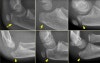

- 영상 검사

주관절의 AP, lateral view로 진단이 충분합니다.

X-ray : 주두 골절(Olecranon fracture)

X-ray(소아) : 주두 골절(Olecranon fracture)